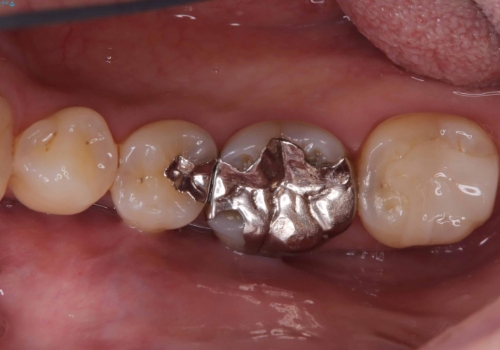

【セラミックインレー・フルジルコニアクラウン】2本の銀歯の下が虫歯に

- 銀歯2本の下が虫歯になっていたので、フルジルコニアクラウンとセラミックインレーで治療を行いました。